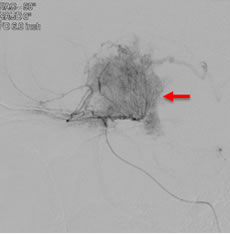

当院での症例をお示しします。症例は66才女性、進行する左眼の視力(左:手動弁)、視野障害にて当院来院。MRIにて赤矢印のように左蝶形骨内側に大きな腫瘍を認めます。開頭手術治療前に腫瘍の栄養血管にカテーテルを入れて、固体塞栓物質を造影剤と混ぜて注入します。最後に再開通しない様プラチナコイルを留置して終了します。その2日後に腫瘍摘出を行いましたが、出血は少量で輸血も行っておりません。視力も左は1.5まで改善し、患者さんは元気で退院しました。(図1-a・b、図2-a・b、図3-a・b、図4-a・b)

図4-a:術前血管撮影, 栄養血管からの造影では赤矢印の様に腫瘍濃染を認める。 |

図4-b:塞栓後血管撮影, 黄色矢印の様に腫瘍濃染は消失した。 |